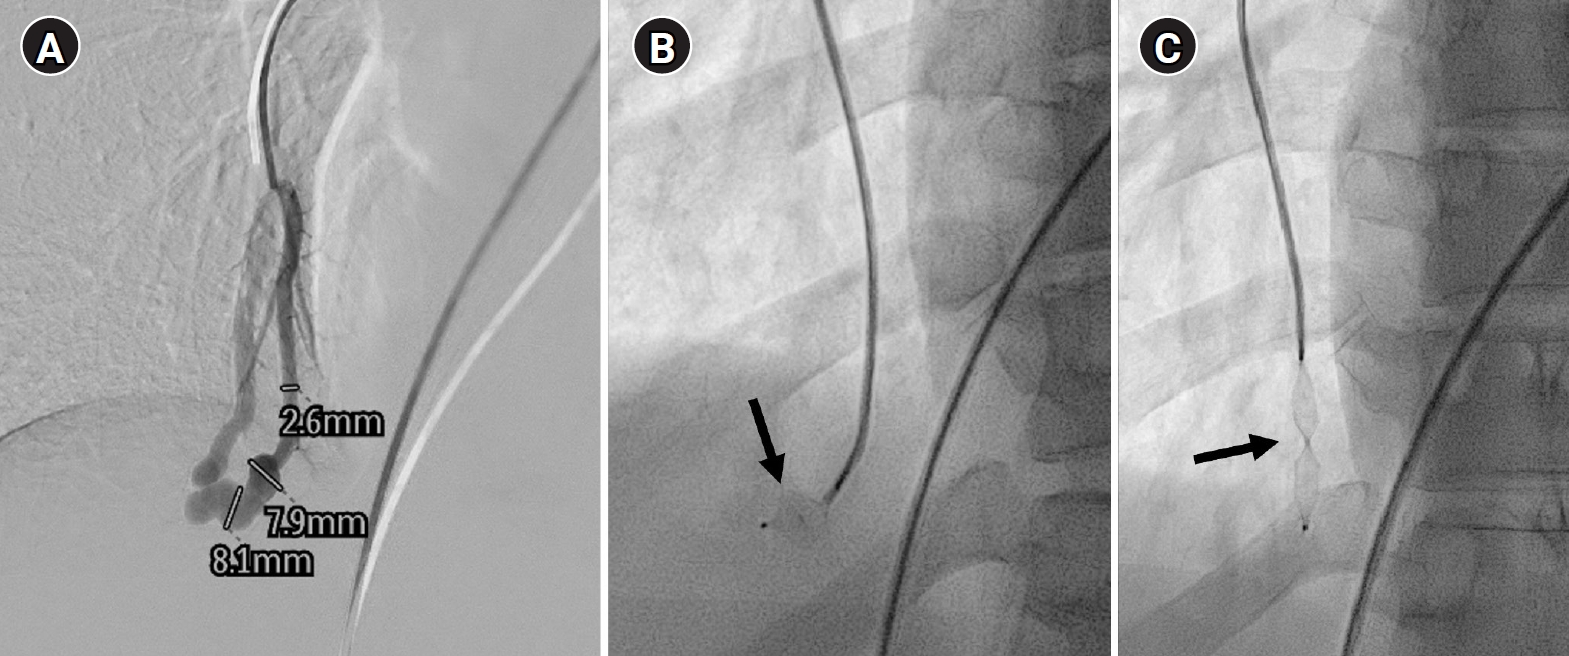

Agitated saline bubble echocardiography images. (A) After injection of agitated saline bubbles into a peripheral vein, echogenic bubbles are seen filling the right heart. Under normal conditions, the bubbles are completely filtered by the pulmonary capillary bed, and no bubbles appear in the left cardiac chambers. (B) After the appearance of bubbles in the right cardiac chambers, bubbles are subsequently observed in the left cardiac chambers after three cardiac cycles, indicating the presence of an extracardiac shunt (pulmonary arteriovenous malformation). RA, right atrium; RV, right ventricle; LA, left atrium; LV, left ventricle.

Fig. 1. Agitated saline bubble echocardiography images. (A) After injection of agitated saline bubbles into a peripheral vein, echogenic bubbles are seen filling the right heart. Under normal conditions, the bubbles are completely filtered by the pulmonary capillary bed, and no bubbles appear in the left cardiac chambers. (B) After the appearance of bubbles in the right cardiac chambers, bubbles are subsequently observed in the left cardiac chambers after three cardiac cycles, indicating the presence of an extracardiac shunt (pulmonary arteriovenous malformation). RA, right atrium; RV, right ventricle; LA, left atrium; LV, left ventricle.